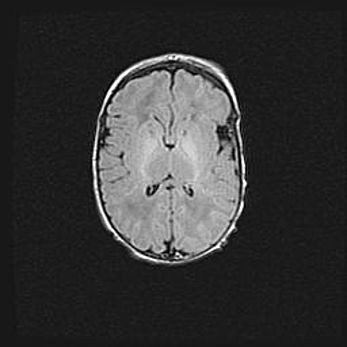

Множественные кисты обоих полушарий головного мозга, наибольшая из них в правой затылочной области. Ассиметричная атрофическая гидроцефалия.

Возраст: 7 месяцев

Вес: 5660 г

Пол: мужской

Окружность головы: 41,5 см

Срок гестации: 28-29 недель

Кисты головного мозга развиваются в результате многоочаговых некрозов вещества мозга и возникают вследствие перенесенной перинатальной инфекции, менингитов, энцефалитов, асфиксии, родовой травмы, расстройств мозгового кровообращения различного генеза. Образованию кист в веществе головного мозга плодов и новорожденных способствуют такие факторы, как высокое содержание в нем воды, недостаточная (или отсутствие) миелинизация и слабая астроглиальная реакция на повреждение.

Кисты могут сочетаться с гидроцефалией и другими поражениями головного мозга.